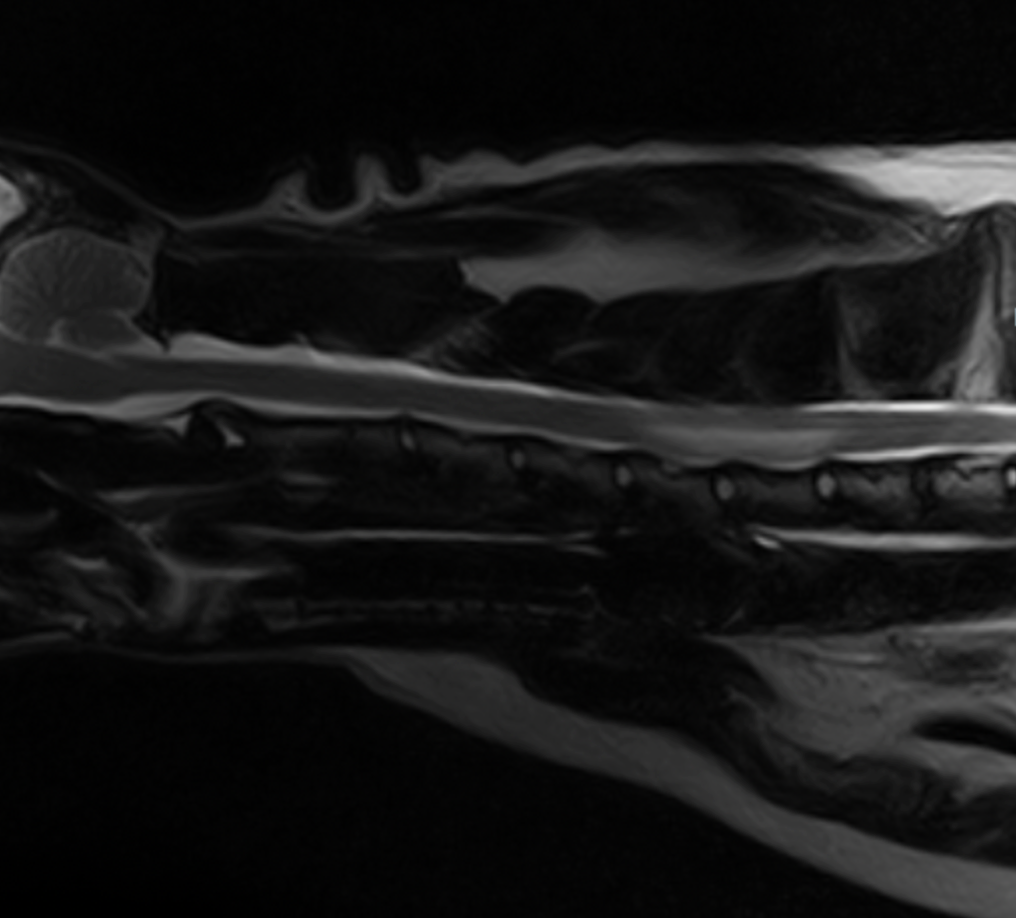

In early 2022, Veterinary Emergency + Referral Centre (VERC) became home to Hawaii’s first Hallmarq 1.5T small animal MRI. It was a milestone for veterinary imaging in the islands! However, before that, many pets with possible brain, spinal cord, or soft tissue injuries were limited to CT scans. And, although fast, CT is not always able to catch the subtle but critical lesions that MRI can detect. The absence of high‑field MRI was proving to be a barrier to diagnosis and effective treatment.

Hallmarq’s small animal 1.5T MRI system is unique in that it is purpose‑built for pets and their anatomy. It is not a repurposed human MRI machine which is often the case. Instead, it delivers superb, detailed images that are needed for a definitive diagnosis in veterinary practice. Features like the V‑shaped patient bed, veterinary‑specific coils, and advanced channels deliver superior imaging of the brain, spinal cord, and delicate structures in animals of all sizes.

Both Hallmarq’s MRI and Remote Operations provide the tools needed by Dr Williamson to support her specialist knowledge. At VERC, advanced imaging is paired with expert interpretation. As a result, neurological conditions once difficult to detect are now diagnosed earlier, treated more effectively, and managed with greater confidence. In the case of beloved cat Oliver, MRI made all the difference to his diagnosis: